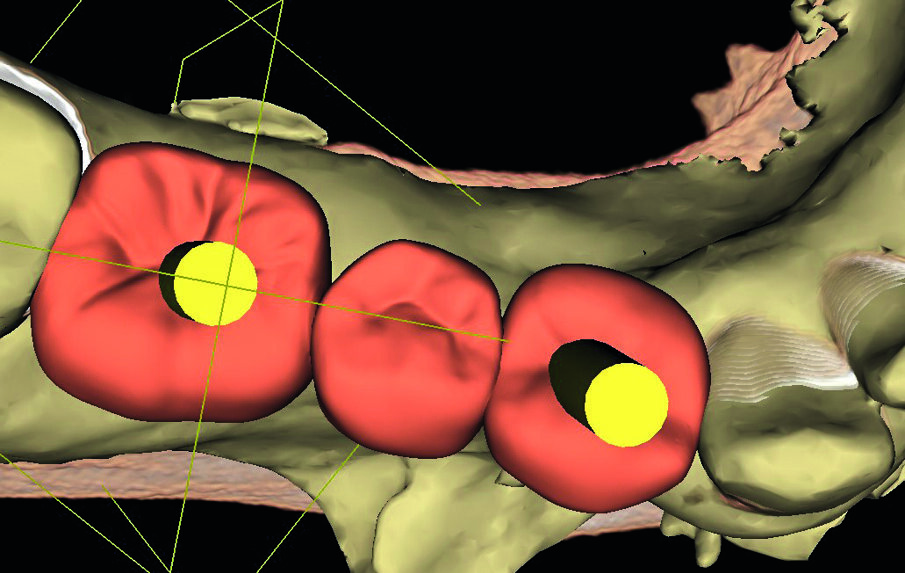

Matching of Orthophos SL 3D data with the prosthetic proposal in Galileos Implant.

Prosthetic alignment of the implant in planning.